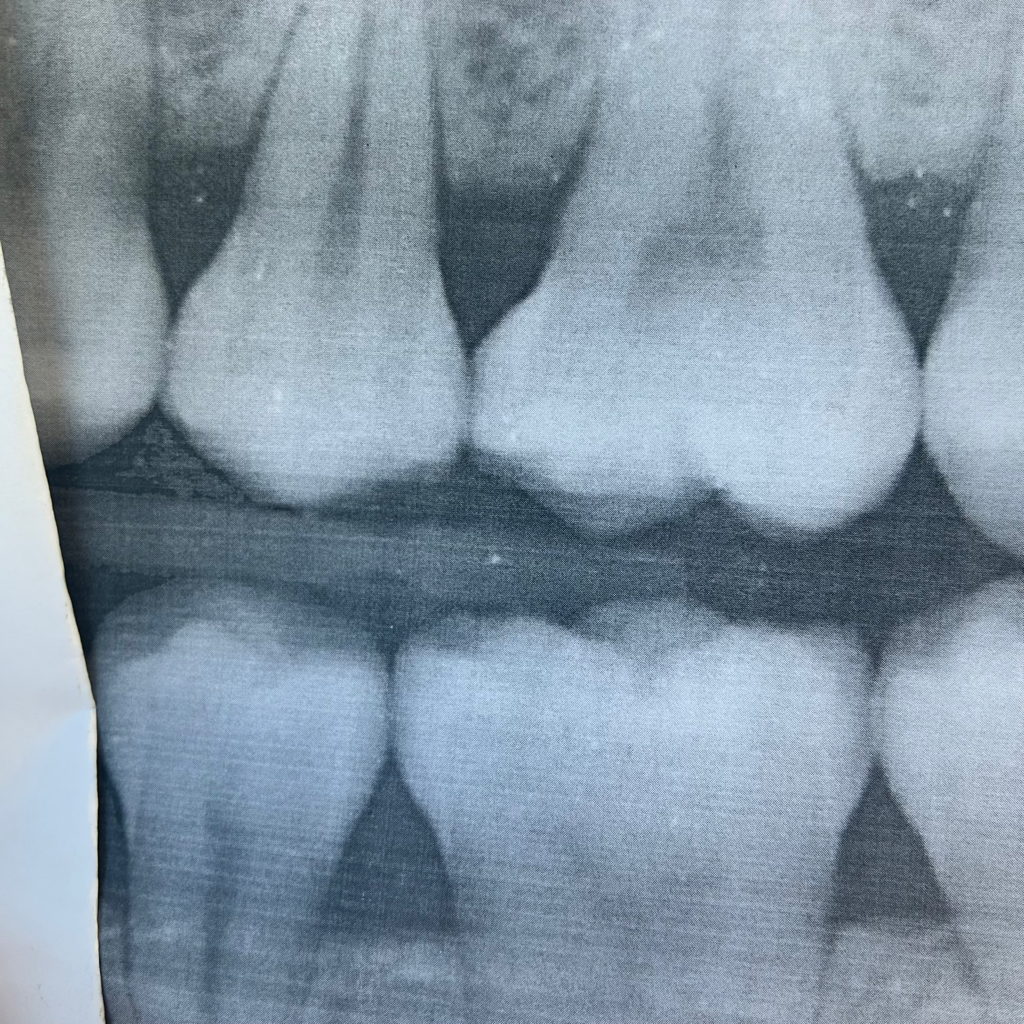

첫 번째 치과에서는 인접면 충치가 있고

사진상 아래처럼 썩어서 신경과 거리가 1mm밖에 남지 않았다, 빨리 인레이를 해야한다 했고

• 1번 째 사진

파노라마만으로는 인접면 충치를 판단하기는 어렵습니다. 아래 작은 사진을 보게되면 깊은 충치가 보이진 않습니다.